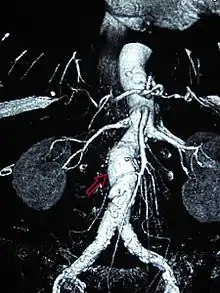

CT reconstruction image of an abdominal aortic aneurysm

The risk of rupture of an AAA is related to its diameter; once the aneurysm reaches about 5 cm, the yearly risk of rupture may exceed the risks of surgical repair for an average-risk patient. Rupture risk is also related to shape; so-called "fusiform" (long) aneurysms are considered less rupture-prone than "saccular" (shorter, bulbous) aneurysms, the latter having more wall tension in a particular location in the aneurysm wall.[9]